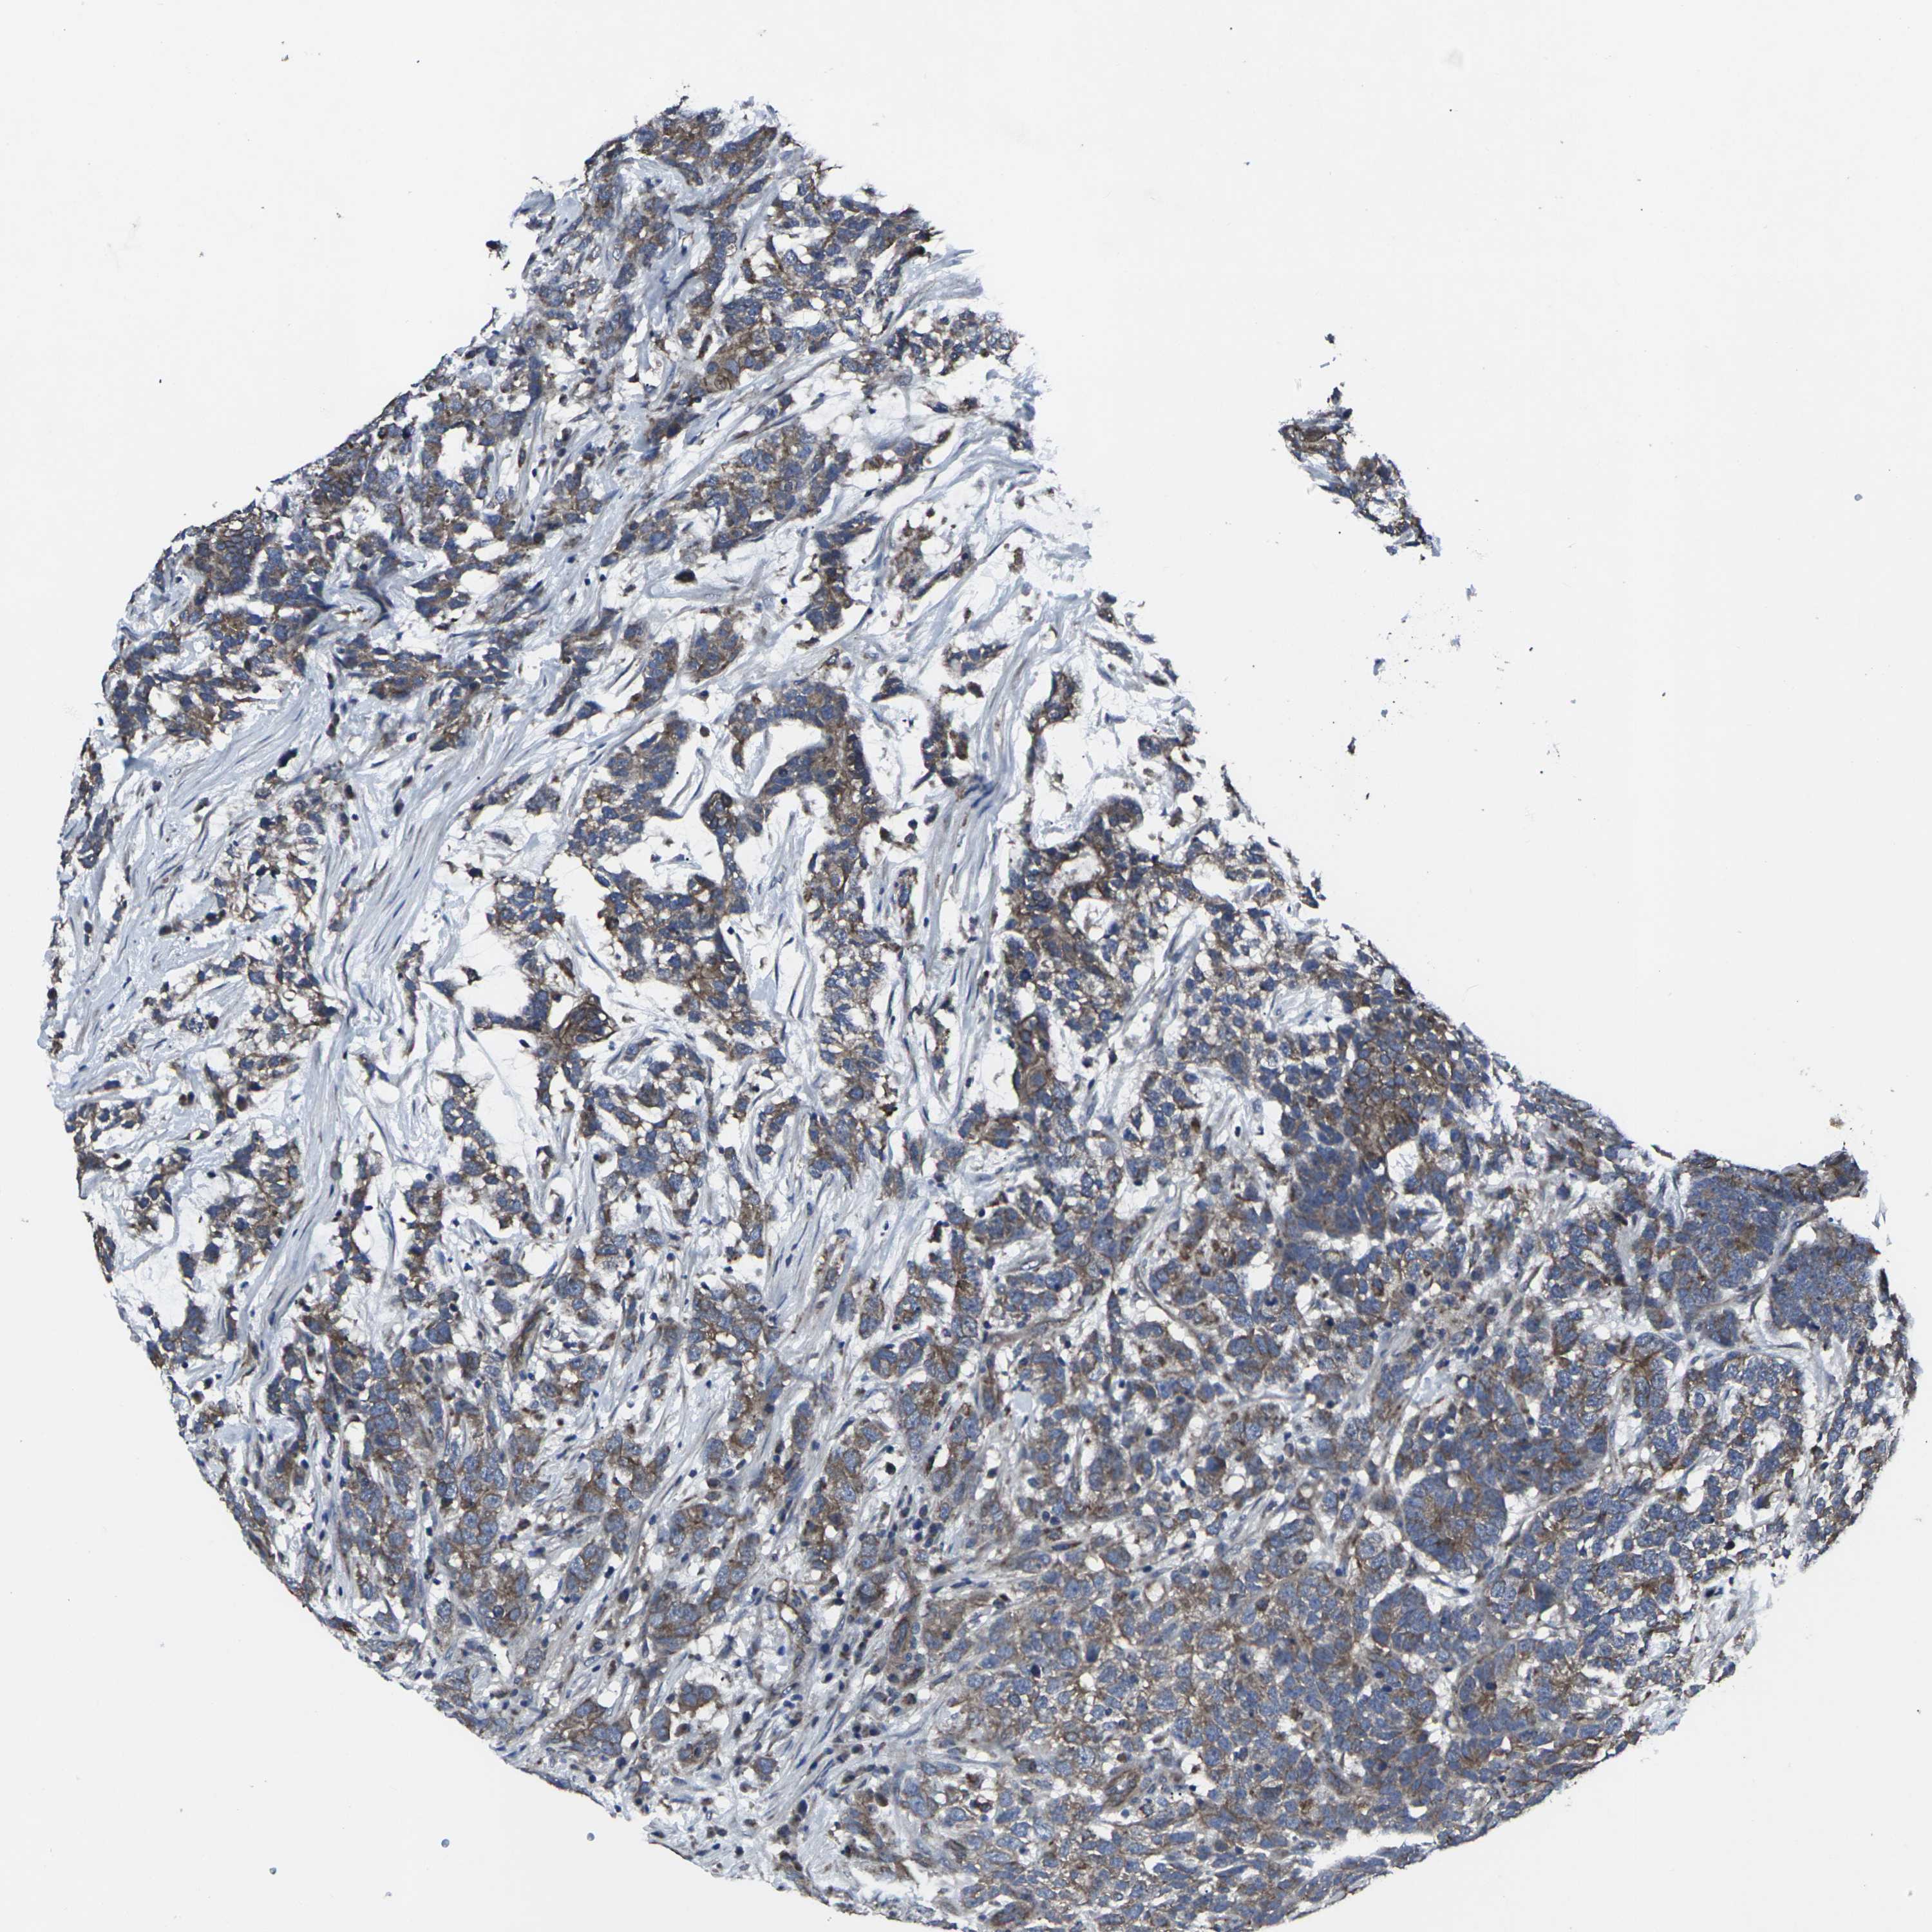

TESTIS CANCER - Protein expressioni

A mouse-over function shows sample information and annotation data. Click on an image to view it in a full screen mode. Samples can be filtered based on level of antibody staining by selecting one or several of the following categories: high, medium, low and not detected. The assay and annotation is described here.

Note that samples used for immunohistochemistry by the Human Protein Atlas do not correspond to samples in the TCGA dataset.

Antibody stainingi

Antibody staining in the annotated cell types in the current human tissue is reported as not detected, low, medium, or high, based on conventional immunohistochemistry profiling in selected tissues. This score is based on the combination of the staining intensity and fraction of stained cells.

Each image is clickable and will lead to virtual microscopy that enables deeper exploration of all samples and also displays staining intensity scores, fraction scores and subcellular localization as well as patient and tissue information for each sample.

Antibody HPA063708

Antibody HPA064435

Antibody CAB010297

Staining

High

Medium

Low

Not detected

Intensity

Strong

Moderate

Weak

Negative

Quantity

>75%

75%-25%

<25%

None

Location

Nuclear

Cytoplasmic/membranous

Cytoplasmic/membranous,nuclear

Seminoma, NOS

Carcinoma, Embryonal, NOS